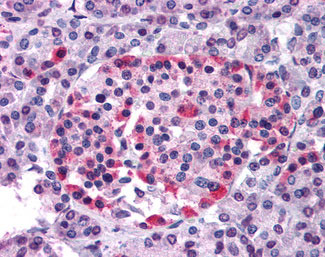

Anti-GPR81 antibody APR15997G IHC of human pancreas. |